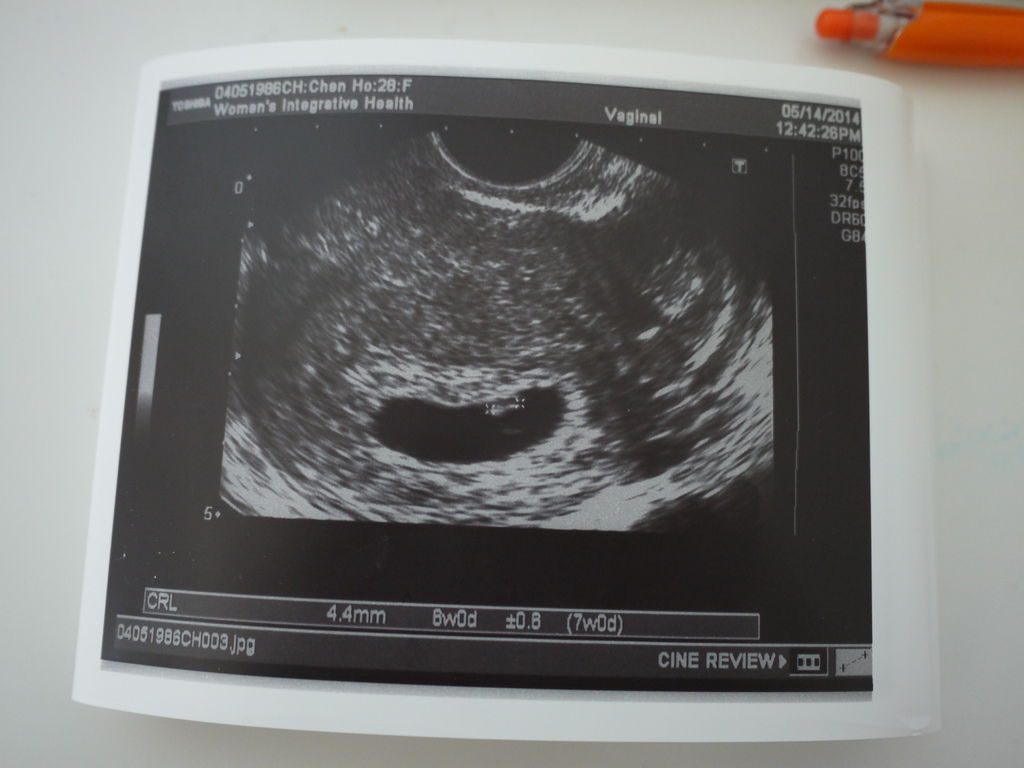

當天的Highlight是 當醫生秀給我們看機器上寶寶一閃一閃的心跳的時候

我們兩個都超興奮的

這麼小的小生命 竟然就已經有心跳了呢

而且我還聽到小小聲的心跳聲

醫生估計寶寶現在才六週而已 等小孩再大一點之後 心跳聲就會很明顯囉